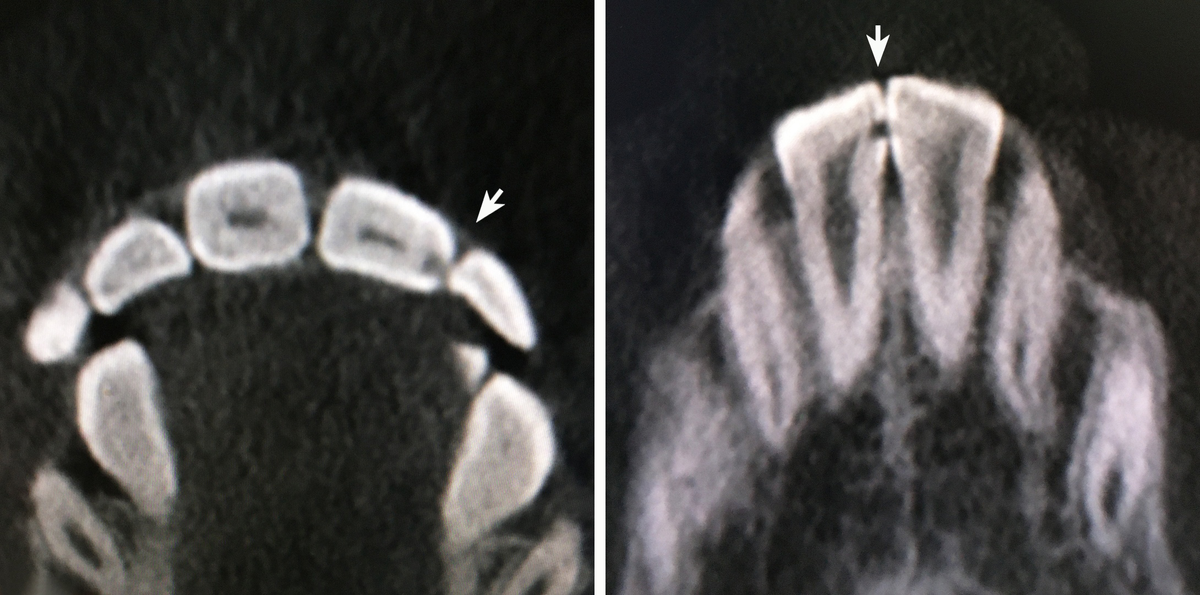

Это компьютерная томография зубов с контактным кариесом.

Даже врач может не увидеть контактный кариес, если не сделать компьютерную томографию. В карусели несколько снимков, на которых он хорошо виден, а при обычном осмотре, был не заметен.